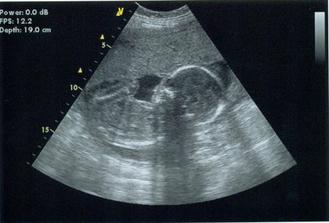

25.3. chtěli jsme s manželem vědět jaký poklad čekáme, ale naše dítko nás chtělo ještě chvíli napínat. A když ho paní doktorka pošťuchovala, tak mě za trest koplo a že prý nic nebude. Tak si ještě počkáme :o)

7.4. jsme byli na velkým ultrazvuku, vše je jak má být :o) A konečně víme, co naše sluníčko bude. Ale jsme tajnůstkáři, takže nikomu neprozradíme ;o)